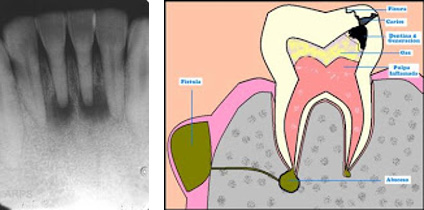

Son susceptibles a todos los procesos inflamatorios e infecciosos que se producen en el órgano dentario, así como a nivel de las estructuras blandas de la cavidad bucal o maxi-lares, tales como: pulpitis, gingivitis, parodontitis, alveolitis, osteítis, cicatrices de exodoncia, así como todos los dientes necrosados, la mala posición y los tratamientos defectuosos elaborados.

- Todos los dientes con una inflamación o infección

En ocasiones existen dientes que aparentemente están sanos y sin embargo pueden constituir focos debido a degeneración pulpar pulpitis crónica).

Todo diente con pulpa necrótica puede tener un foco, muestre o no la radiografía alteraciones óseas en su entorno.

Una endodoncia, o lo que comúnmente se conoce como “matar el nervio”, consiste, a grandes rasgos, en limpiar el tejido pulpar enfermo del diente y rellenarlo de nuevo con material biocompatible para posteriormente sellarlo. Éste es uno de [...]